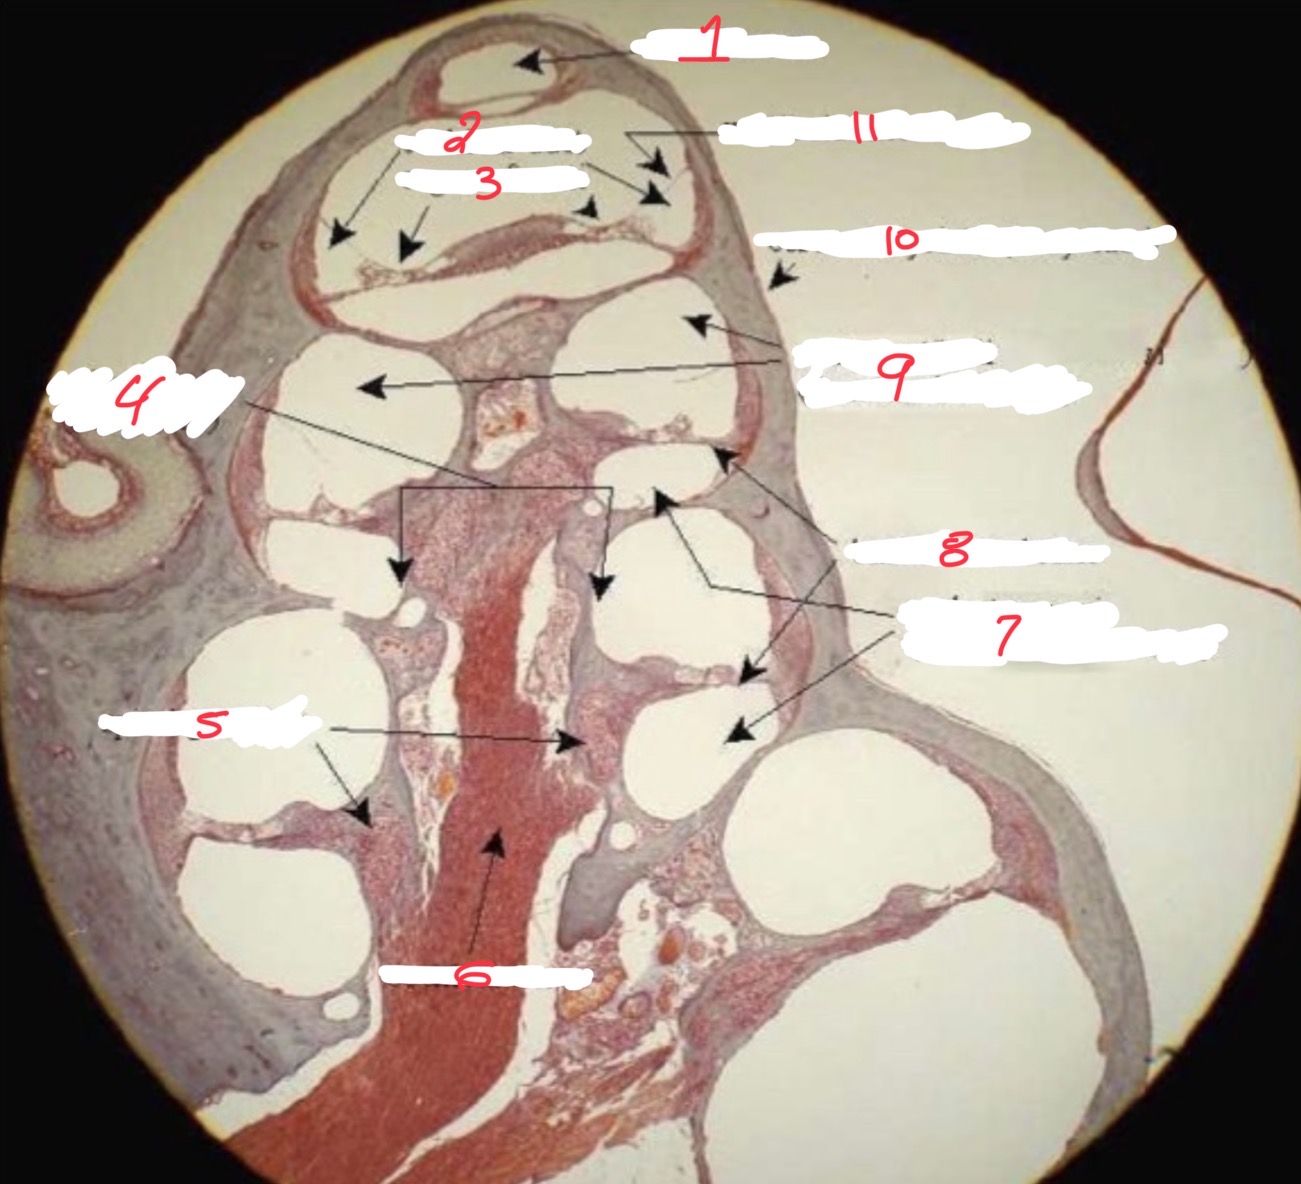

1

Helicotrema

2

Cochlear duct

3

Organ of corti

4

spiral lamina

5

Spiral ganglion

6

Cochlear nerve

7

Scala tympani

8

Basilar membrane

9

Scala vestibuli

10

Osseus labyrinth

11

Vestibular membrane

What is this

Cochlear cross section